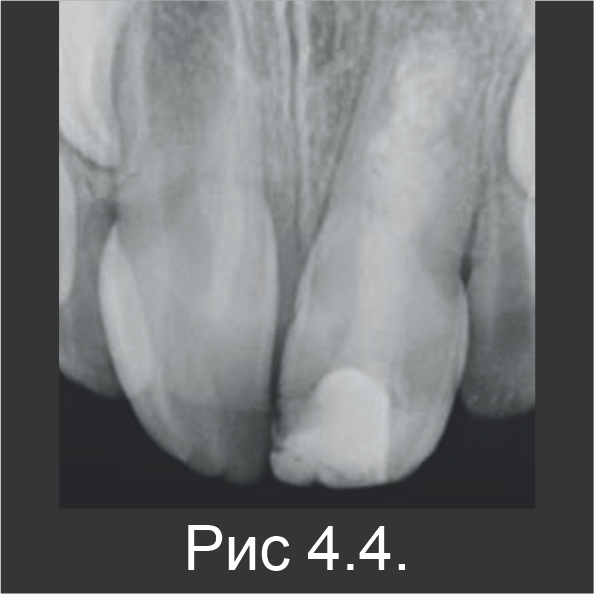

В ходе следующего посещения гидроксид кальция заменили материалом Biodentine™ (рис. 4.3). С помощью контрольного рентгенографического обследования, выполненного через 6 (рис. 4.4) и 18 месяцев (рис. 4.5), установили, что апексогенез зуба 21 продолжается и является сопоставимым с зубом 11, который не лечили (рис. 4.6).